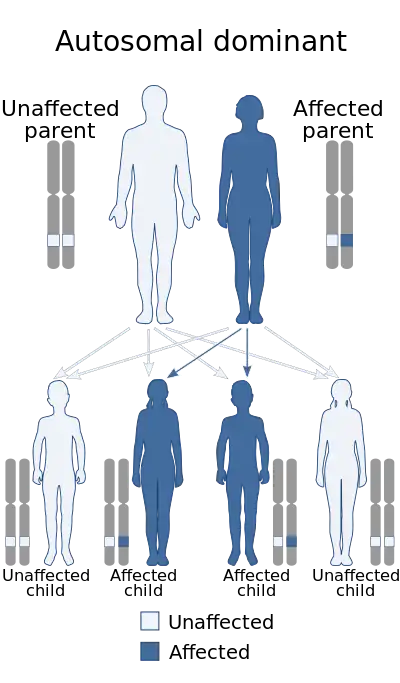

Hajdu–Cheney syndrome is a monogenic disorder. The disorder is inherited and controlled by a single pair of genes. A single copy of the mutant gene on an autosome causes HCS. HCS is an autosomal dominant disorder, only one parent with the defective gene is needed to pass the disorder to the offspring.